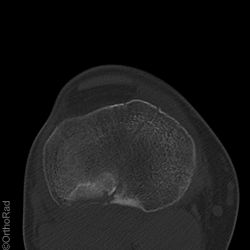

Tibiakopffraktur (nicht disloziert)